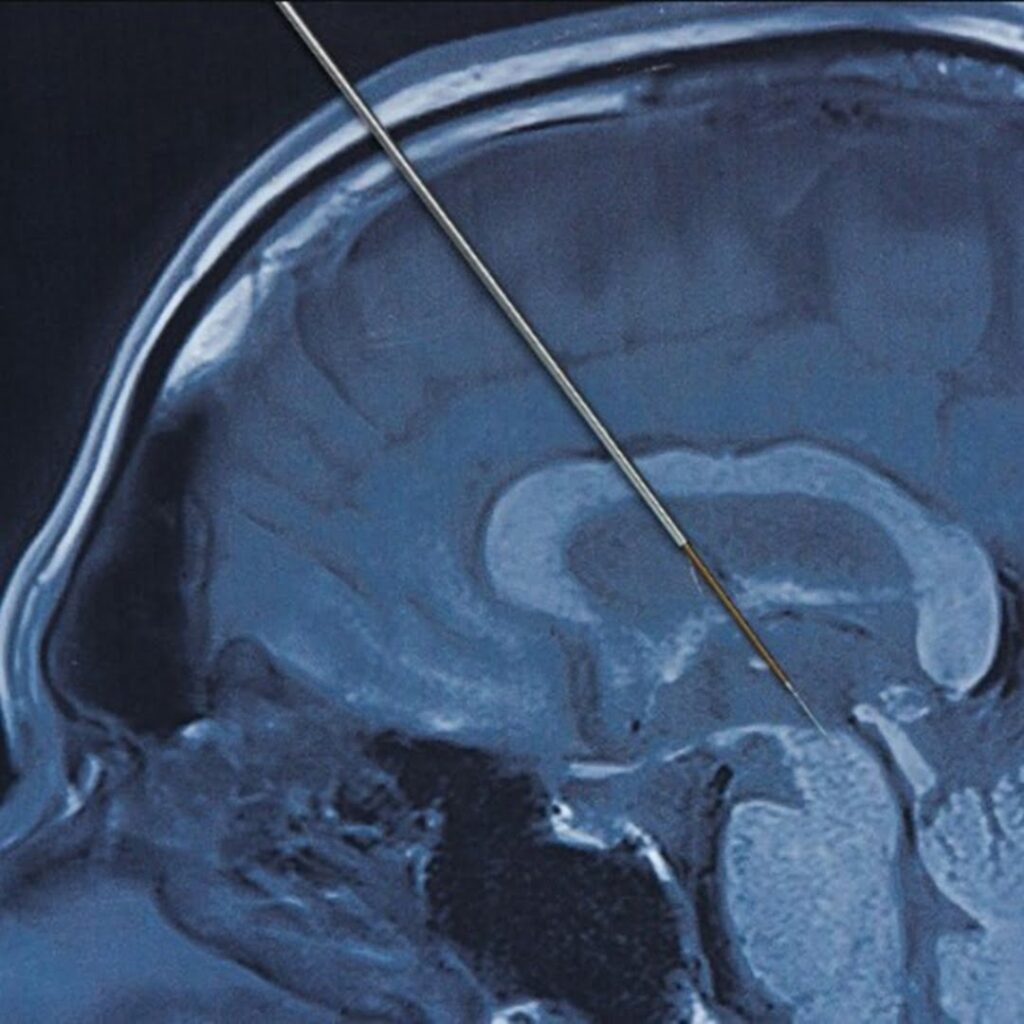

El neurotransmisor Picostim es fabricado por la compañía británica Amber Therapeutics. Durante la cirugía, Tisdall y su equipo insertaron dos electrodos profundamente en el cerebro de Oran hasta llegar al tálamo, un centro altamente conectado en el cerebro. Los cables, que necesitaban ser colocados con una precisión de menos de un milímetro, se conectaron al neuroestimulador.

Este dispositivo de 3.5 cm cuadrados y 0.6 cm de grosor se colocó en un hueco en el cráneo de Oran donde se había removido el hueso y se ancló con tornillos al cráneo circundante. Puede recargarse a través de auriculares portátiles. El implante proporciona una estimulación eléctrica constante y suave a su cerebro con el objetivo de bloquear las vías eléctricas que permiten que se produzcan las convulsiones.